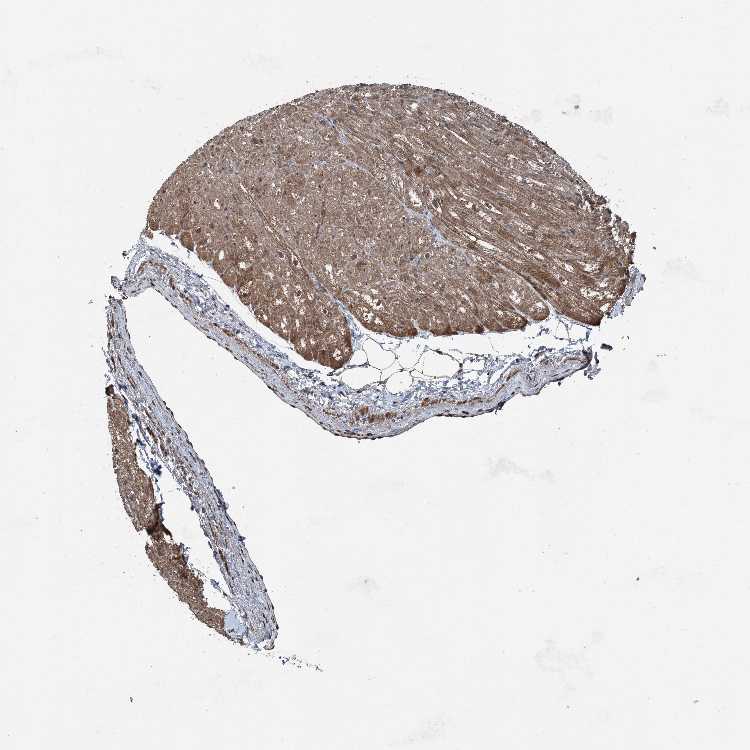

TISSUE PRIMARY DATA HEART MUSCLE Show tissue menu

HEART MUSCLE - Antibody stainingi

Antibody staining in the annotated cell types in the current human tissue is reported as not detected, low, medium, or high, based on conventional immunohistochemistry profiling in selected tissues. This score is based on the combination of the staining intensity and fraction of stained cells.

Each image is clickable and will lead to virtual microscopy that enables deeper exploration of all samples and also displays staining intensity scores, fraction scores and subcellular localization as well as patient and tissue information for each sample.

Antibody HPA053761Antibody CAB033687Antibody CAB037077

Cardiomyocytes Not detectedMediumMedium